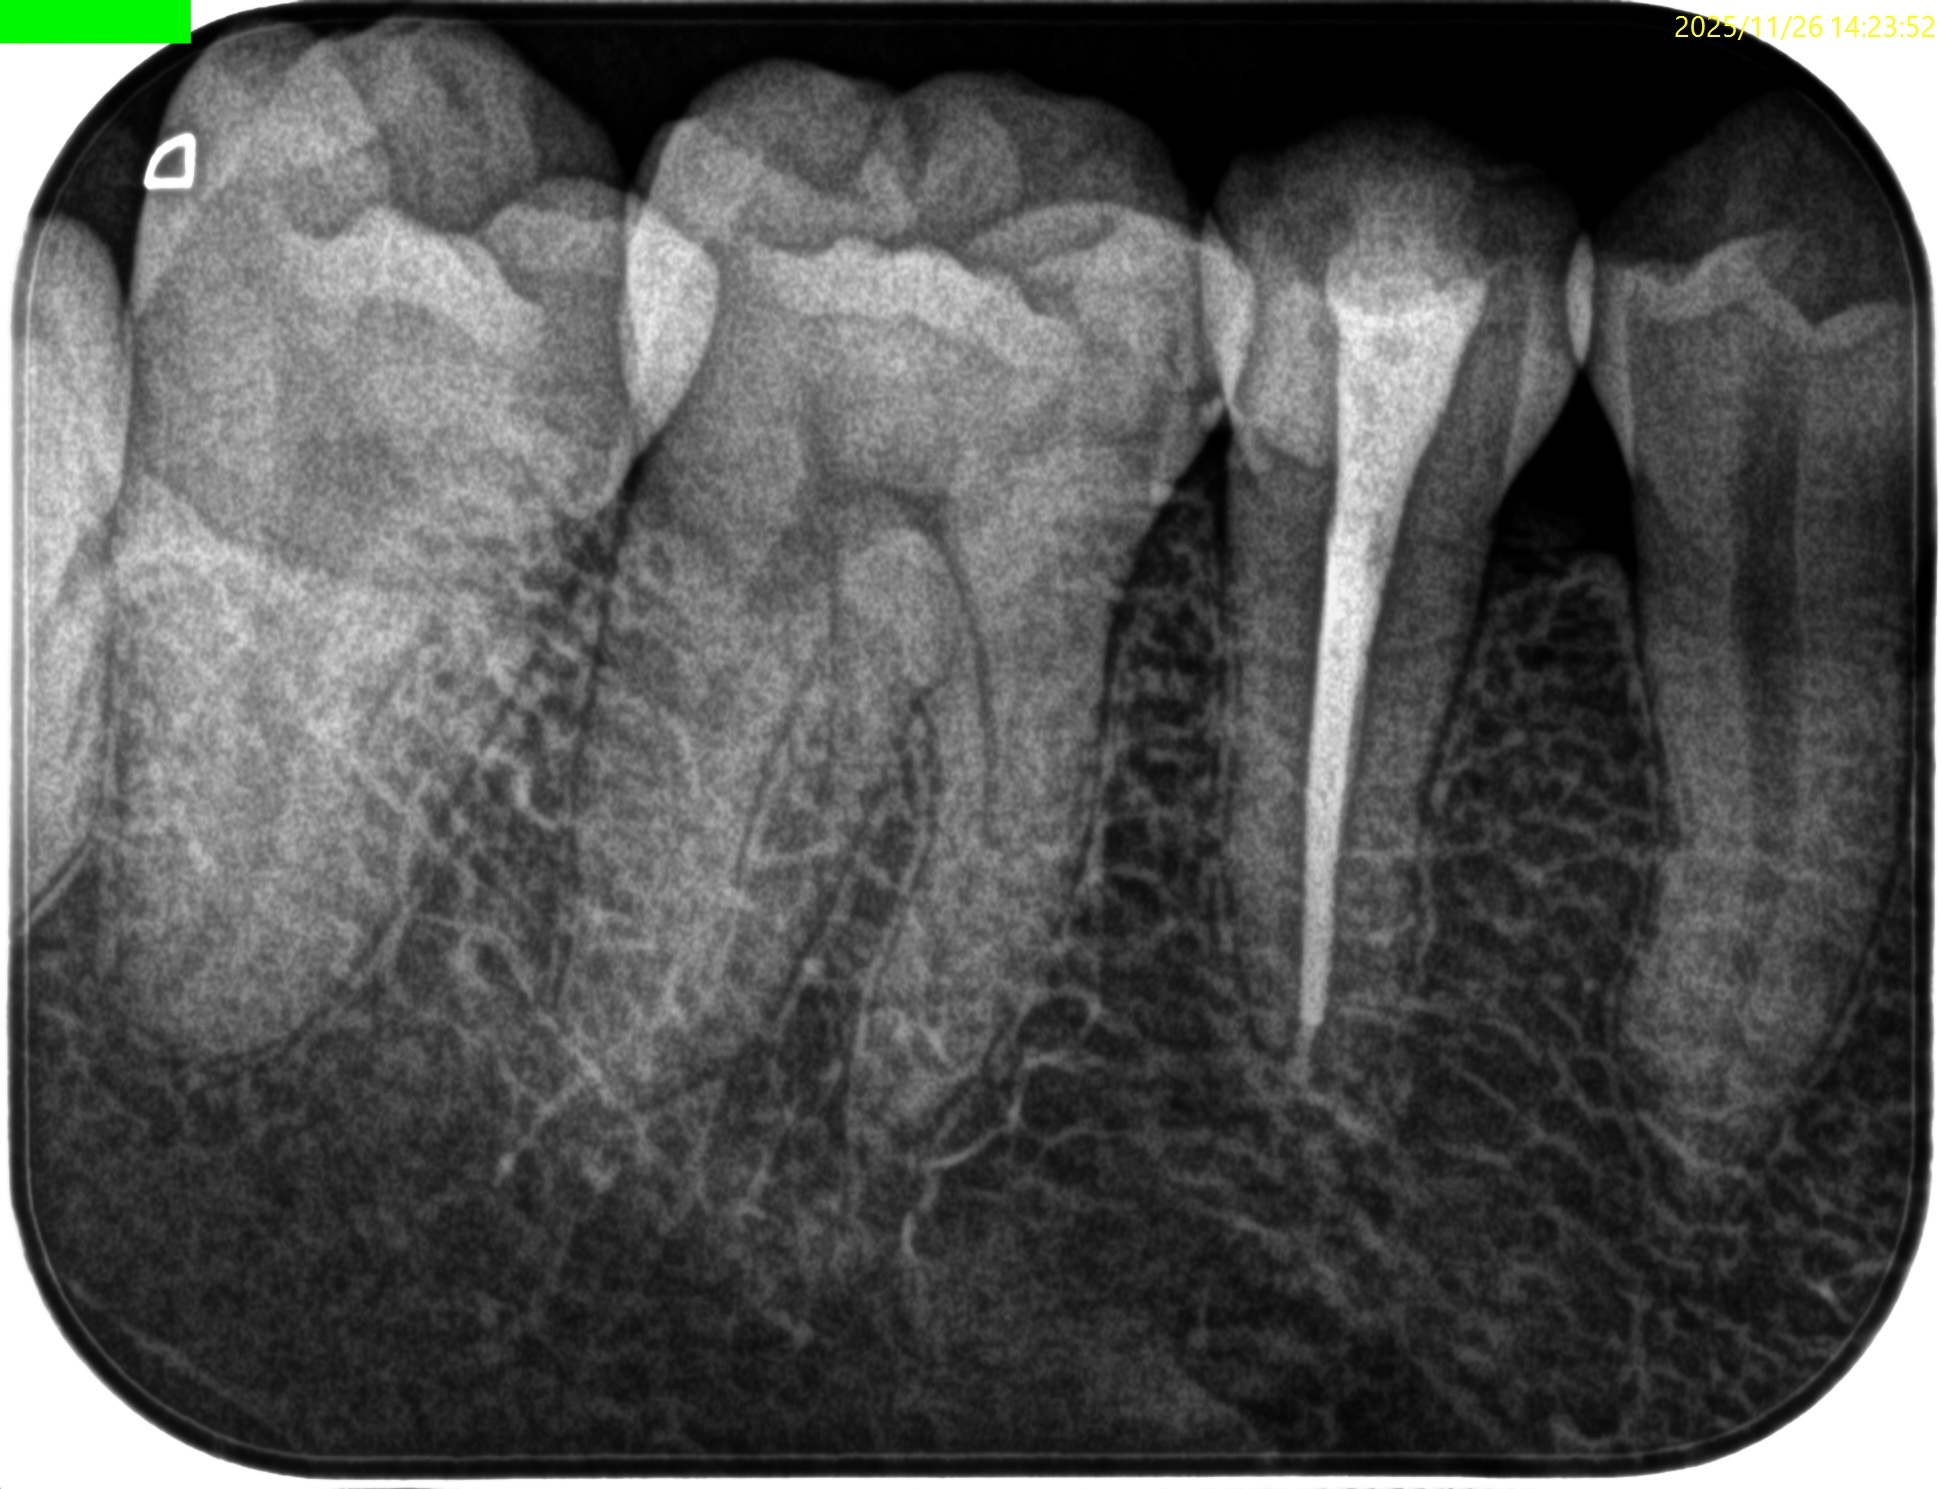

Pre-op Endo test(2025.11.26)

#29に打診痛がある。

紹介元の先生によれば#40.04まで形成したが術後の痛みが続いているという。

根尖病変はない。

根管充填後にPA, CBCTを撮影した。

問題はないだろう。